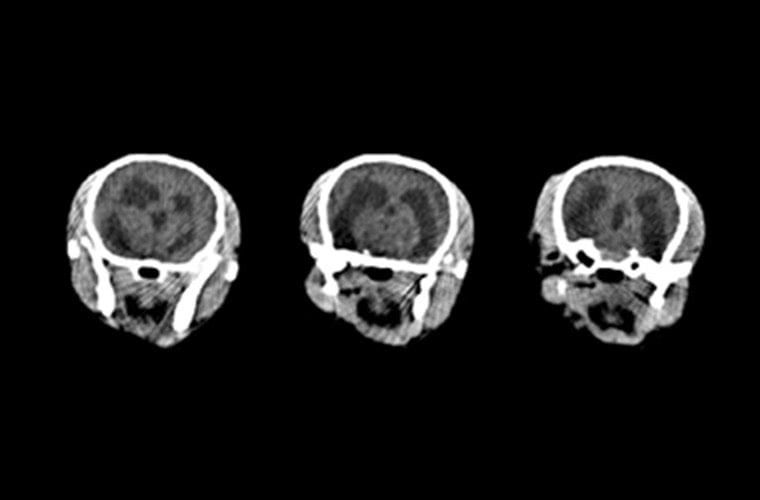

水頭症のチワワの脳内の画像です。通常左右対称であるべき脳室が不対称になって脳脊髄液による圧迫が認められます。